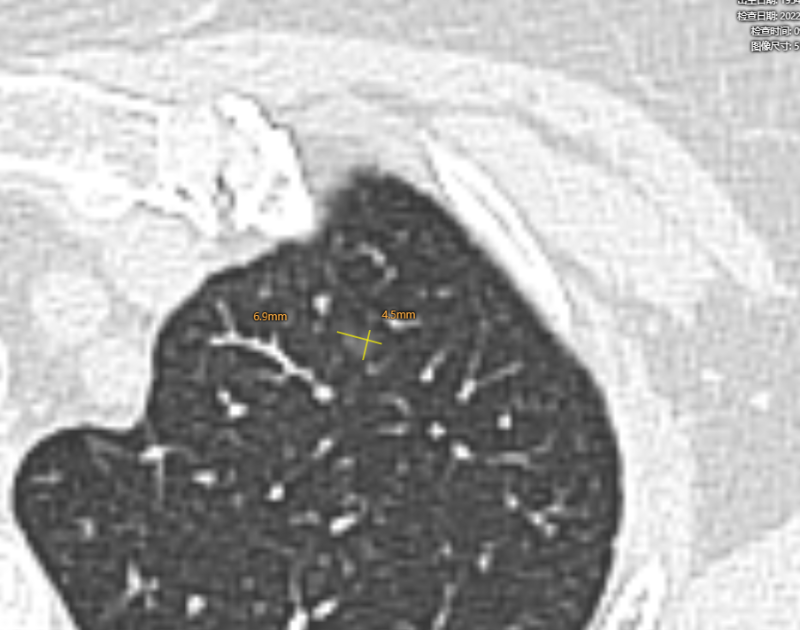

结节1:

2013年

右肺下叶背段纯磨玻璃结节,最大截面约0.9cm×0.9cm,平均CT值约-431Hu,结节呈类圆形,其中可见小空泡,病灶边界清楚,与9年前CT片比较,病灶密度、大小均无明显变化,考虑为微浸润性腺癌-浸润性腺癌,以微浸润性腺癌可能性大。